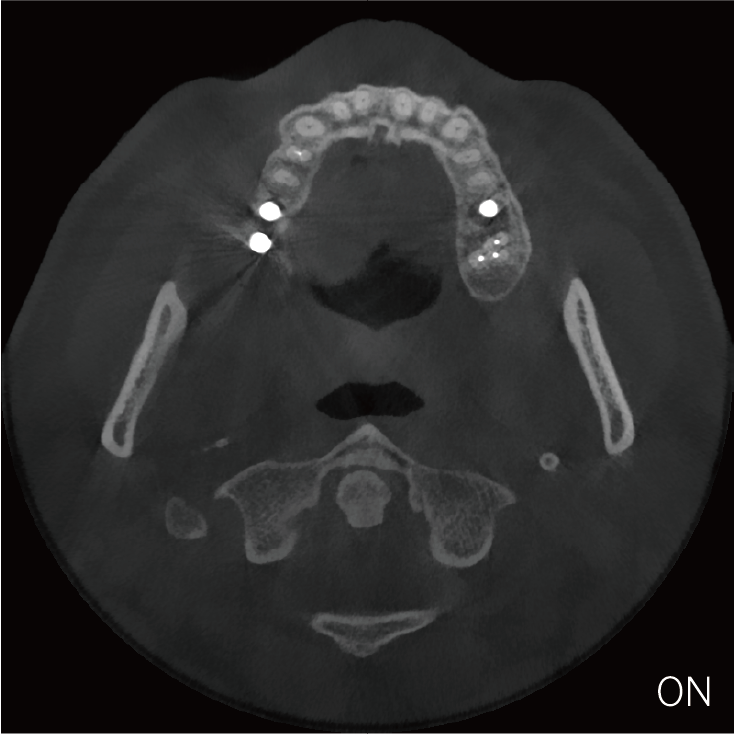

超能去伪 至臻影像

临床样片